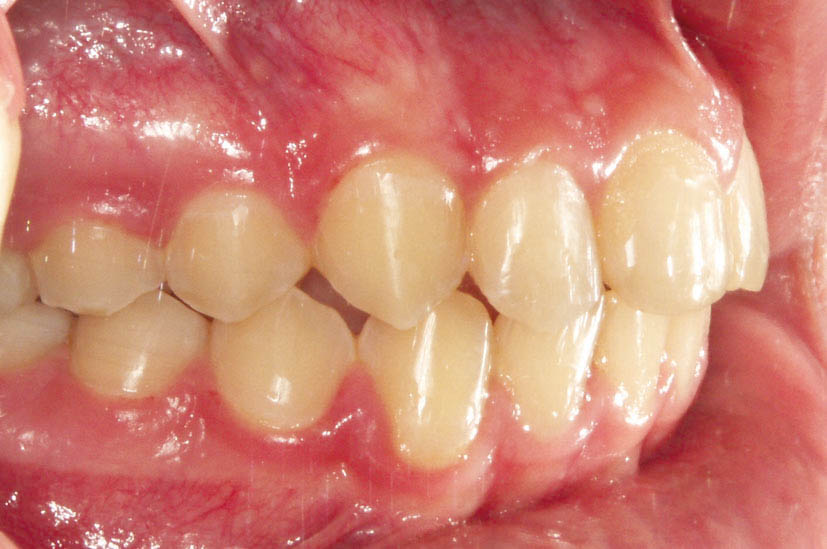

شکل 114-2: 2mm کلاسII در سمت راست

وقتی 2mm کلاسII باشد (شکل 114-2) اگر پرمولرهای بالا را فقط بخاطر 2mm کلاسII بودن بکشید آن موقع برای رسیدن به یک کاسپ کامل کلاسII، مولرهای شما باید 5mm حرکت مزیالی بکنند که از لحاظ مکانیکی کاری بسیار سخت است. بیماران هم شکایتی از اورجت زیاد ندارند چون 2mm کلاسII اورجت زیادی برای آنها درست نمیکند. این بیماران را مانند بیماران کلاسI (منتهی حد مزیالی آن) قبول میکنیم و چون بنا برغیرکشیدنی بودن فک پائین است، لذا بالا را هم غیرکشیدنی درنظر میگیریم و ارتودنسی را تمام میکنیم (شکل 115-2).